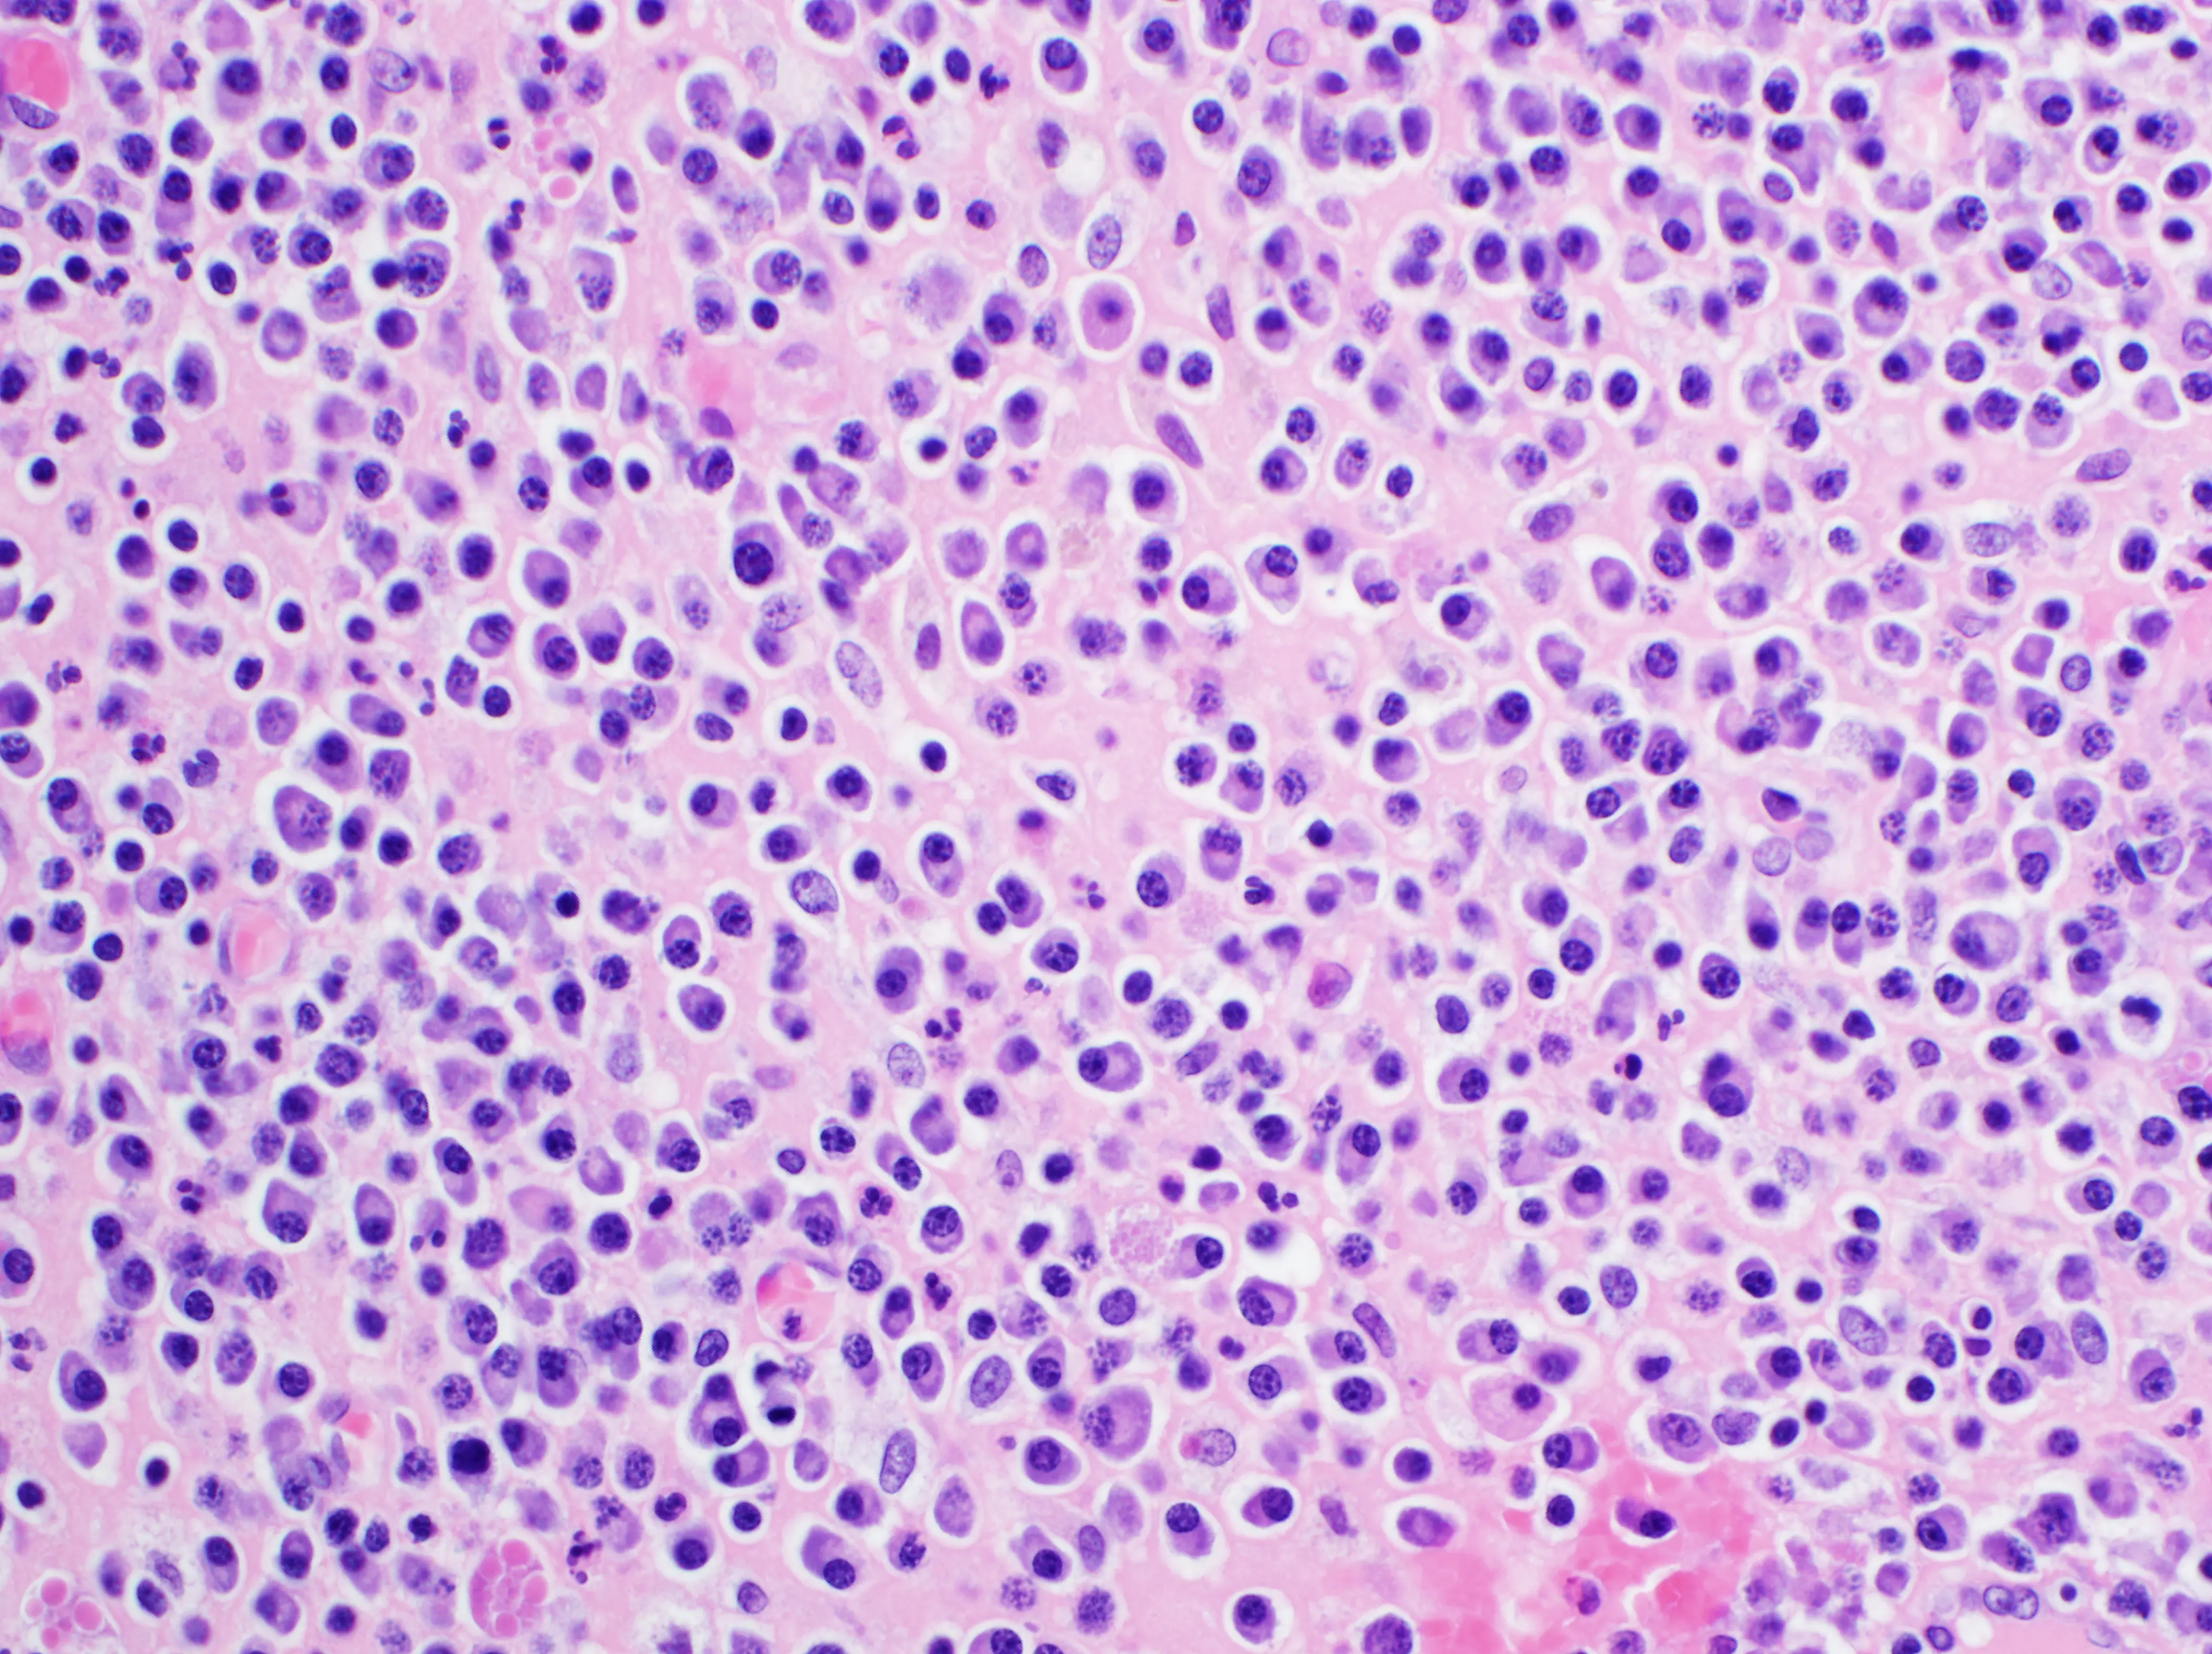

Figure 4 – Large numbers of tubules in the cortex show necrosis, in the form of hypereosinophilic (red staining) cells, fragmentation and lysis of the nuclei. Compare the two necrotic tubules (red arrow) adjacent to a relatively healthy tubule (green arrow).